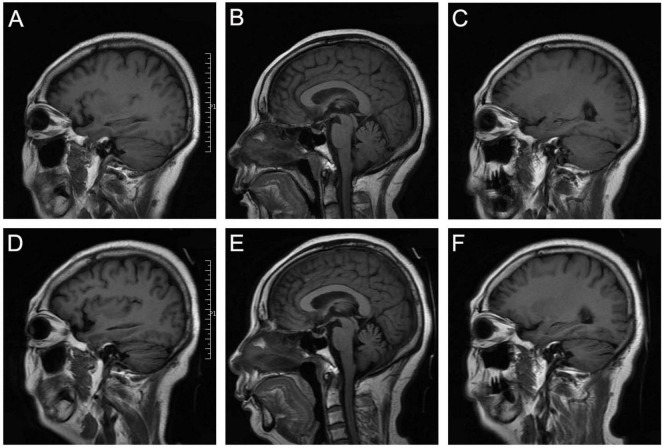

Results: We present a case of anti-mGluR1 encephalitis successfully treated with ofatumumab. During the patient's initial episode, she partially recovered after first-line treatment. She experienced a relapse 6 months later and was treated with ofatumumab, resulting in complete recovery. Forty cases of anti-mGluR1 encephalitis, including our case, were summarized. The prevalence was similar between men and women, with 50% of patients aged 40-59 years. The most common clinical manifestations were ataxia and dysarthria. Cerebrospinal fluid analysis showed normal white blood cell count and IgG index in 37.1% of patients. Almost half of the patients (48.6%) exhibited cerebellar atrophy on cerebral MRI scans at initial presentation or during follow-up. Only 25% of patients recovered completely. According to the modified Rankin Scale (mRS) scores at the last follow-up, patients with poor outcome (n = 13, 32.5%) had a lower proportion of first-line immunotherapy (62%, P = 0.017) and a longer follow-up time (median 36 months, P = 0.038).